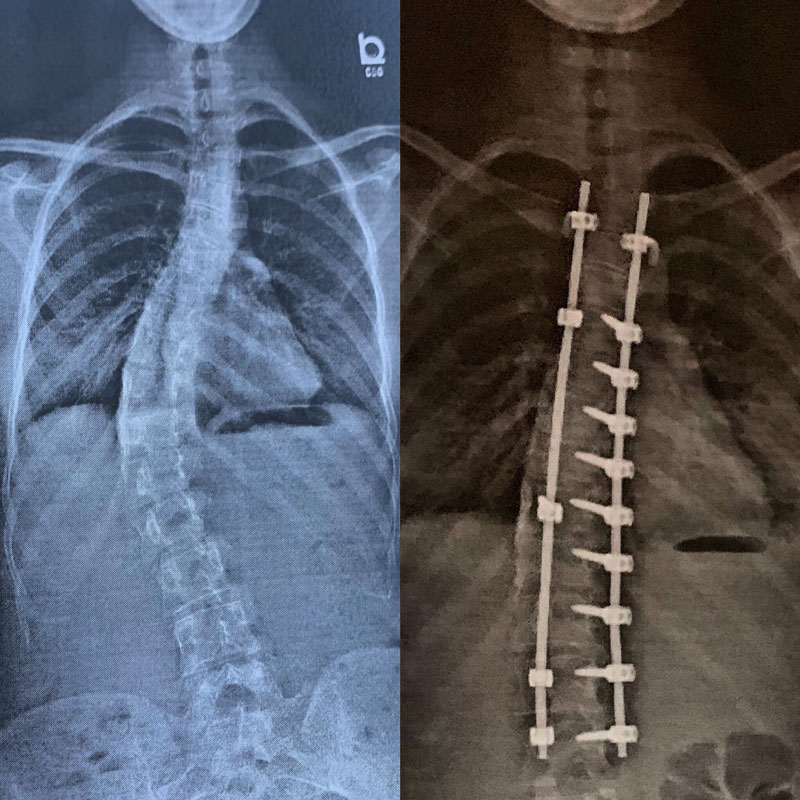

At 9 years old I was diagnosed with scoliosis and being 9 years old I really did not have a clue what I was in store for.

Years passed by and progressively my body became worse, my hips were not even, my shoulders were not even, and my legs were two different lengths. Not only was it visible on the outside, but the pain inside of my body became so unbearable at times, that it was hard to function. For example, I was not able to drive for long periods of time, my back would cause my neck to go stiff almost every day, and I became very very sore just from walking.

Fast forwards 4 years later and my spine caused my body to be in pain every single day, and it was starting to seriously impact my health. At this point the decision to get a spinal fusion was necessary.

This was probably the scariest decision of my life, but also the most bittersweet.

I was finally able to let go of every burden I had faced over the past 10 years, but I had to realize that those moments of pain, hard times, and how you handle your struggles, are what make you, you! Since receiving my spinal fusion, I have continued to book many modeling jobs, as well as I have started my own blog on Instagram to promote body positivity! I am very thankful for this experience.